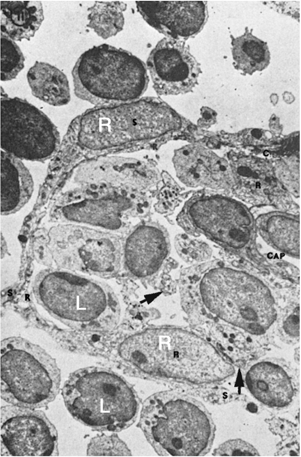

Figure 14.11. Ultrastructure of a lymph node. The area in the center and to the right is occupied by dense lymphoid tissue with many lymphoid cells. It is separated from the sinus (upper area, left, and below) by flat endothelial cells lining the sinus (s), bulky reticular cells (R) bordering the dense lymphoid tissue, and collagenous fibers (c) between the two cellular layers. Arrows indicate collagenous fibers traversing the dense lymphoid tissue. Cap, blood capillary. (From Clark SL Jr. The reticulum of lymph nodes in mice studied with the electron microscope. Am J Anat 1962;110:217, with permission.)